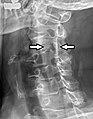

Foraminaintervertebralia.png

Peculiar thoracic vertebrae. Intervertebral foramina are indicated by arrows.